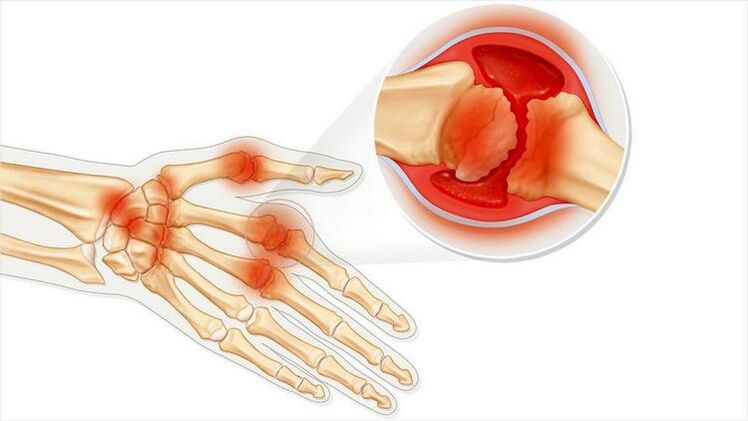

Joint arthritis is a condition of joint inflammation.Mainly expressed as swelling and redness.The inner lining of the joint is destroyed, resulting in pain that is often difficult to simply endure.

Both diseases have a common root in their names "arthron".If you translate it from Greek, you get “joint.”Both diseases are associated with joint problems and pain.Such pathologies occur with acute negative sensations and discomfort.Lesions associated with the cartilaginous layer limit and complicate movement.